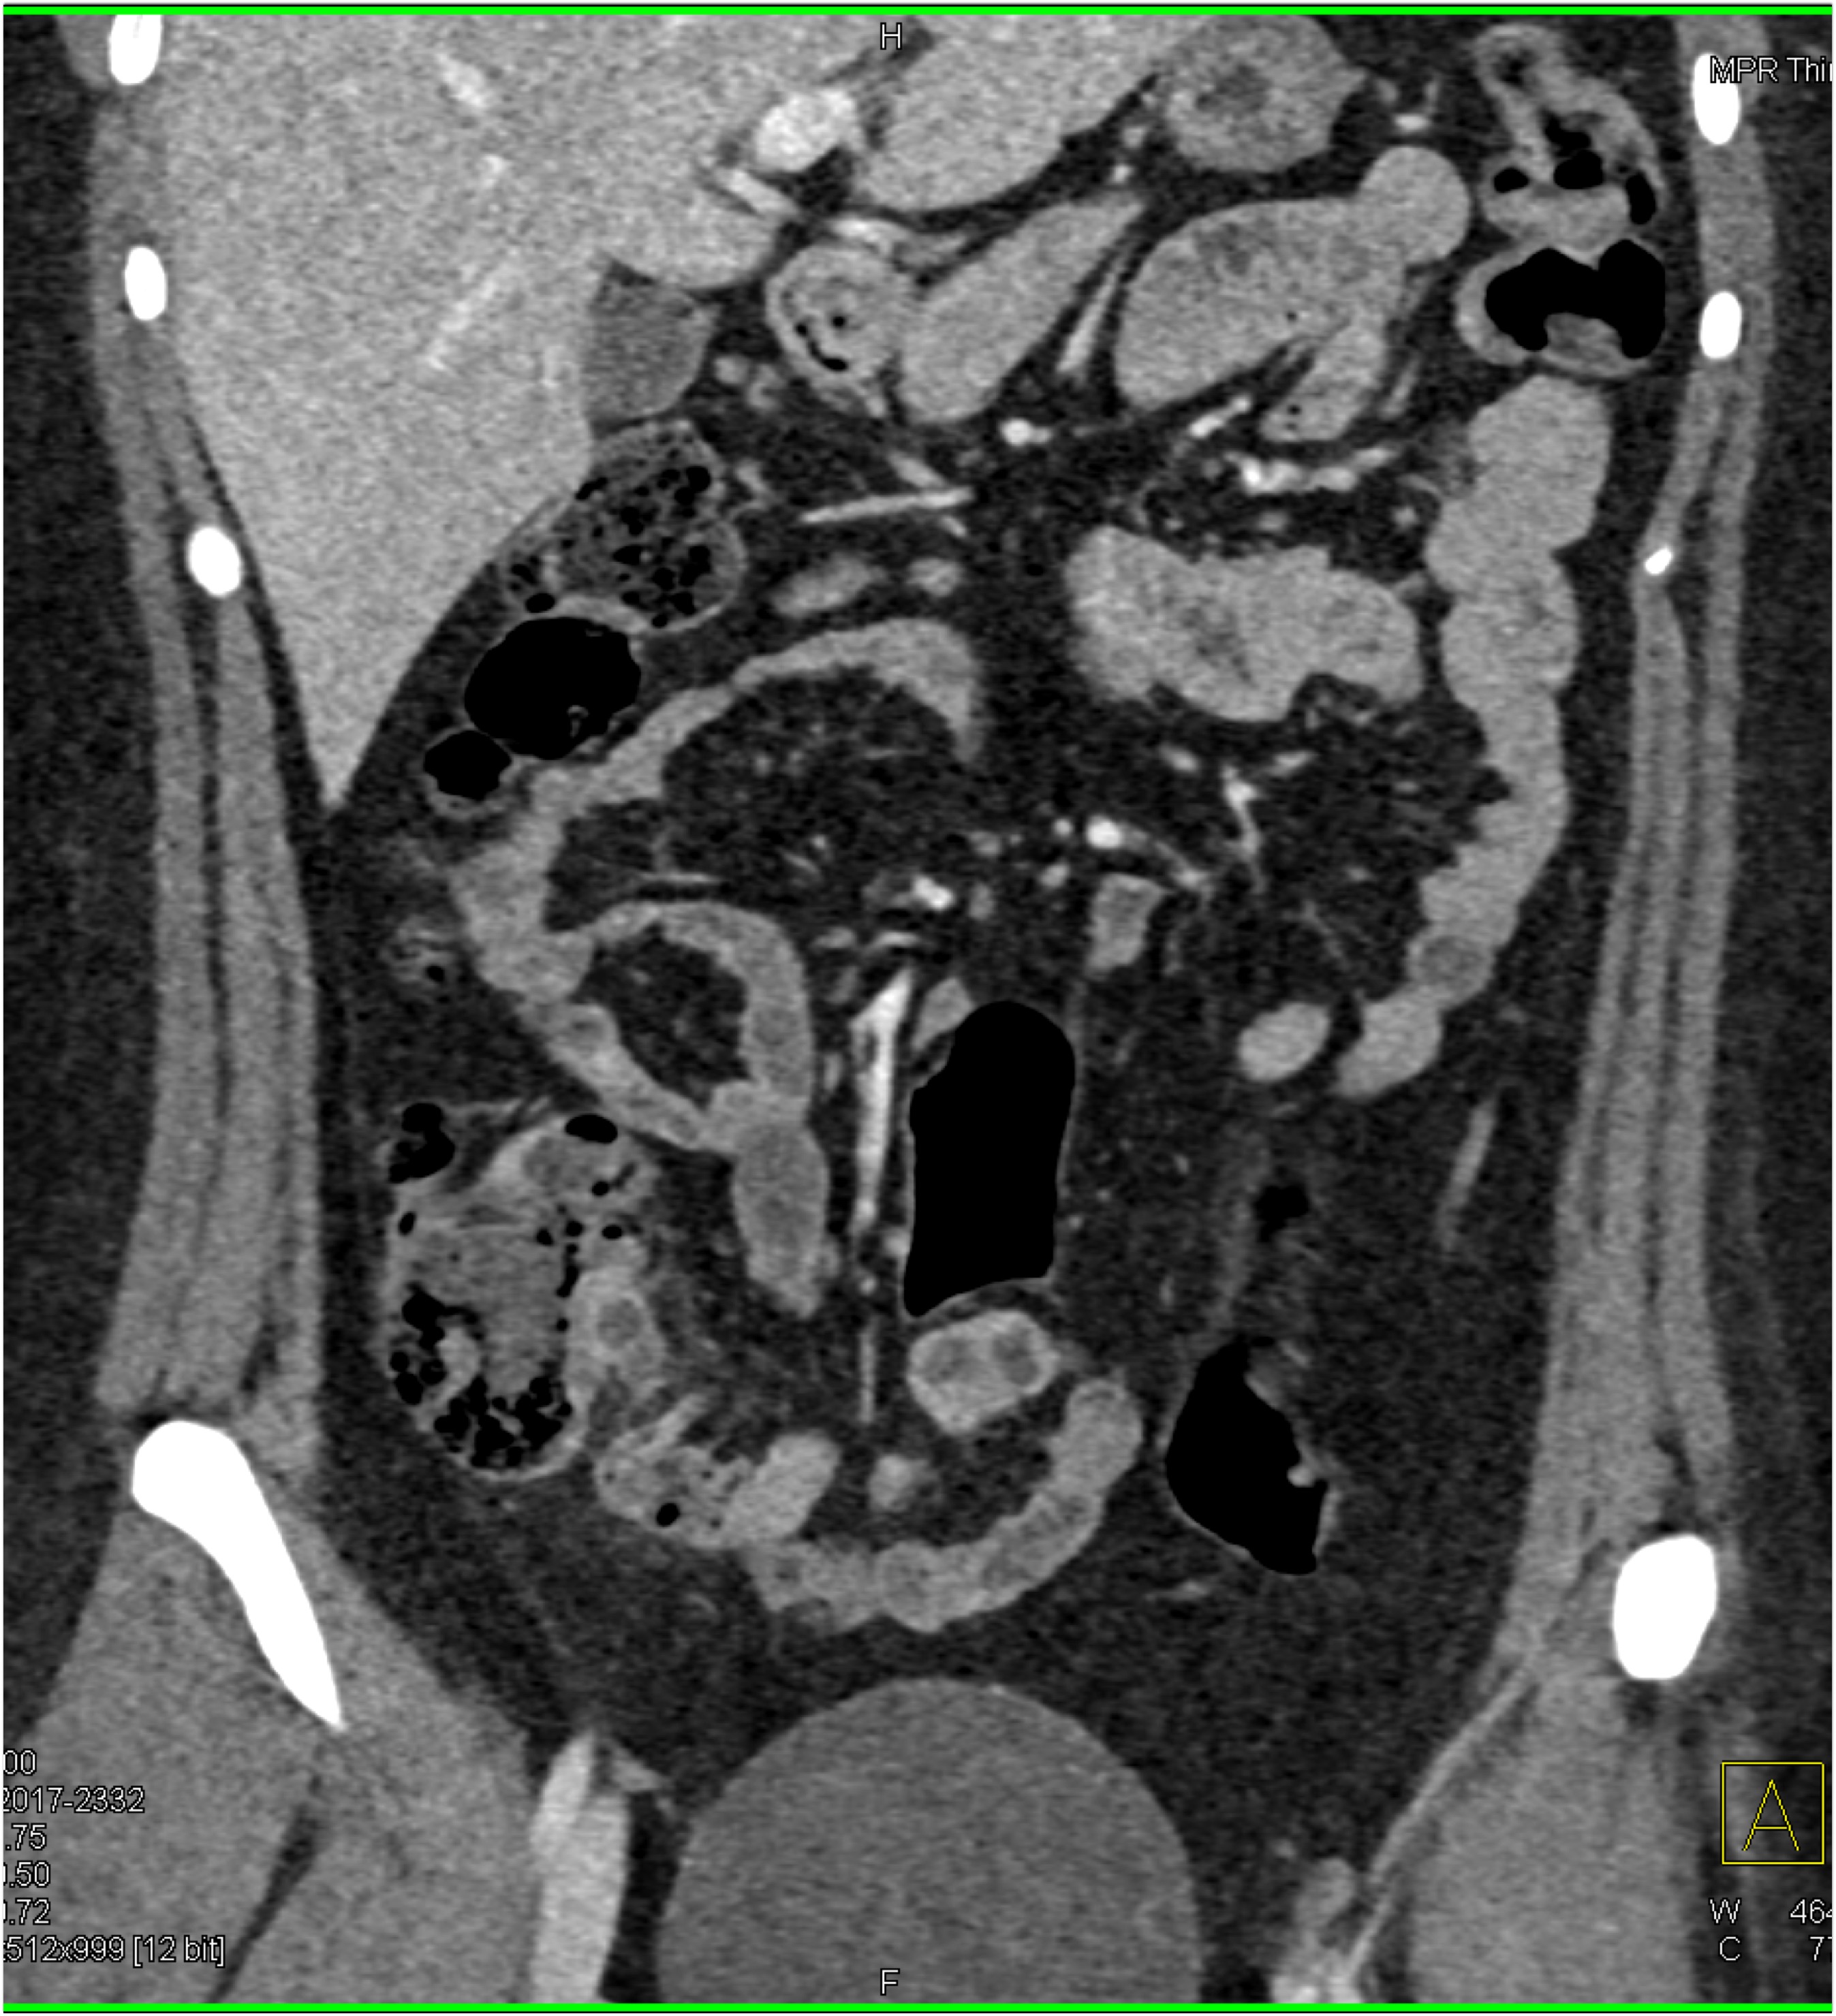

1) The best diagnosis in this patient with RLQ pain and fever is?

acute appendicitis

Crohn’s disease

TB of the ileum